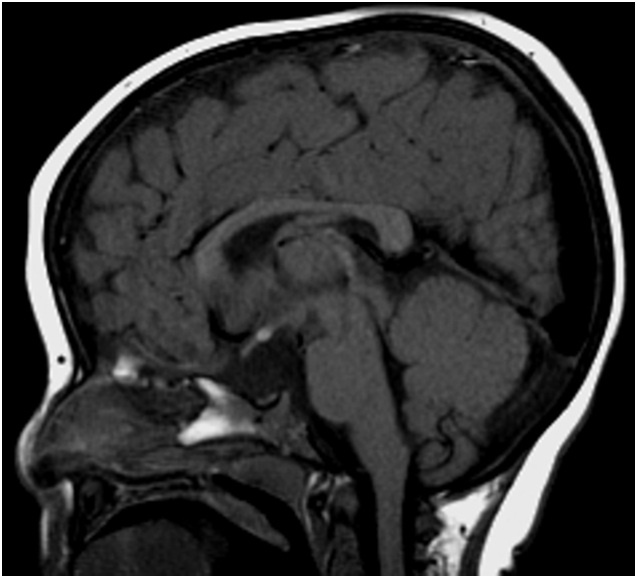

Figure 1: Sagittal T1 weighted Magnetic resonance imaging showing a small anterior pituitary, absent stalk, and normally located posterior pituitary.